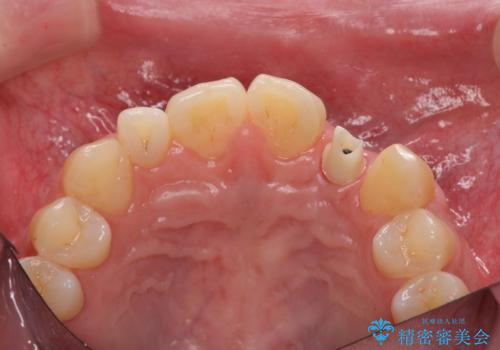

- 前歯の永久歯が元々なく、乳歯を失ったタイミングで前歯の審美性の回復を求めて来院されました。

機能・審美性の回復手段として、インプラント治療・ブリッジ・部分床義歯が考えられます。

それぞれの治療に特徴がありますが、取り外しの必要がなく隣の歯を削る必要も必要ないインプラント治療を選択されました。

前歯部にインプラントを埋入し、きれいに仕上げるためには骨の造成技術や歯肉の厚みを増すような処置を行い、インプラント周囲の環境を整備することが肝要です。